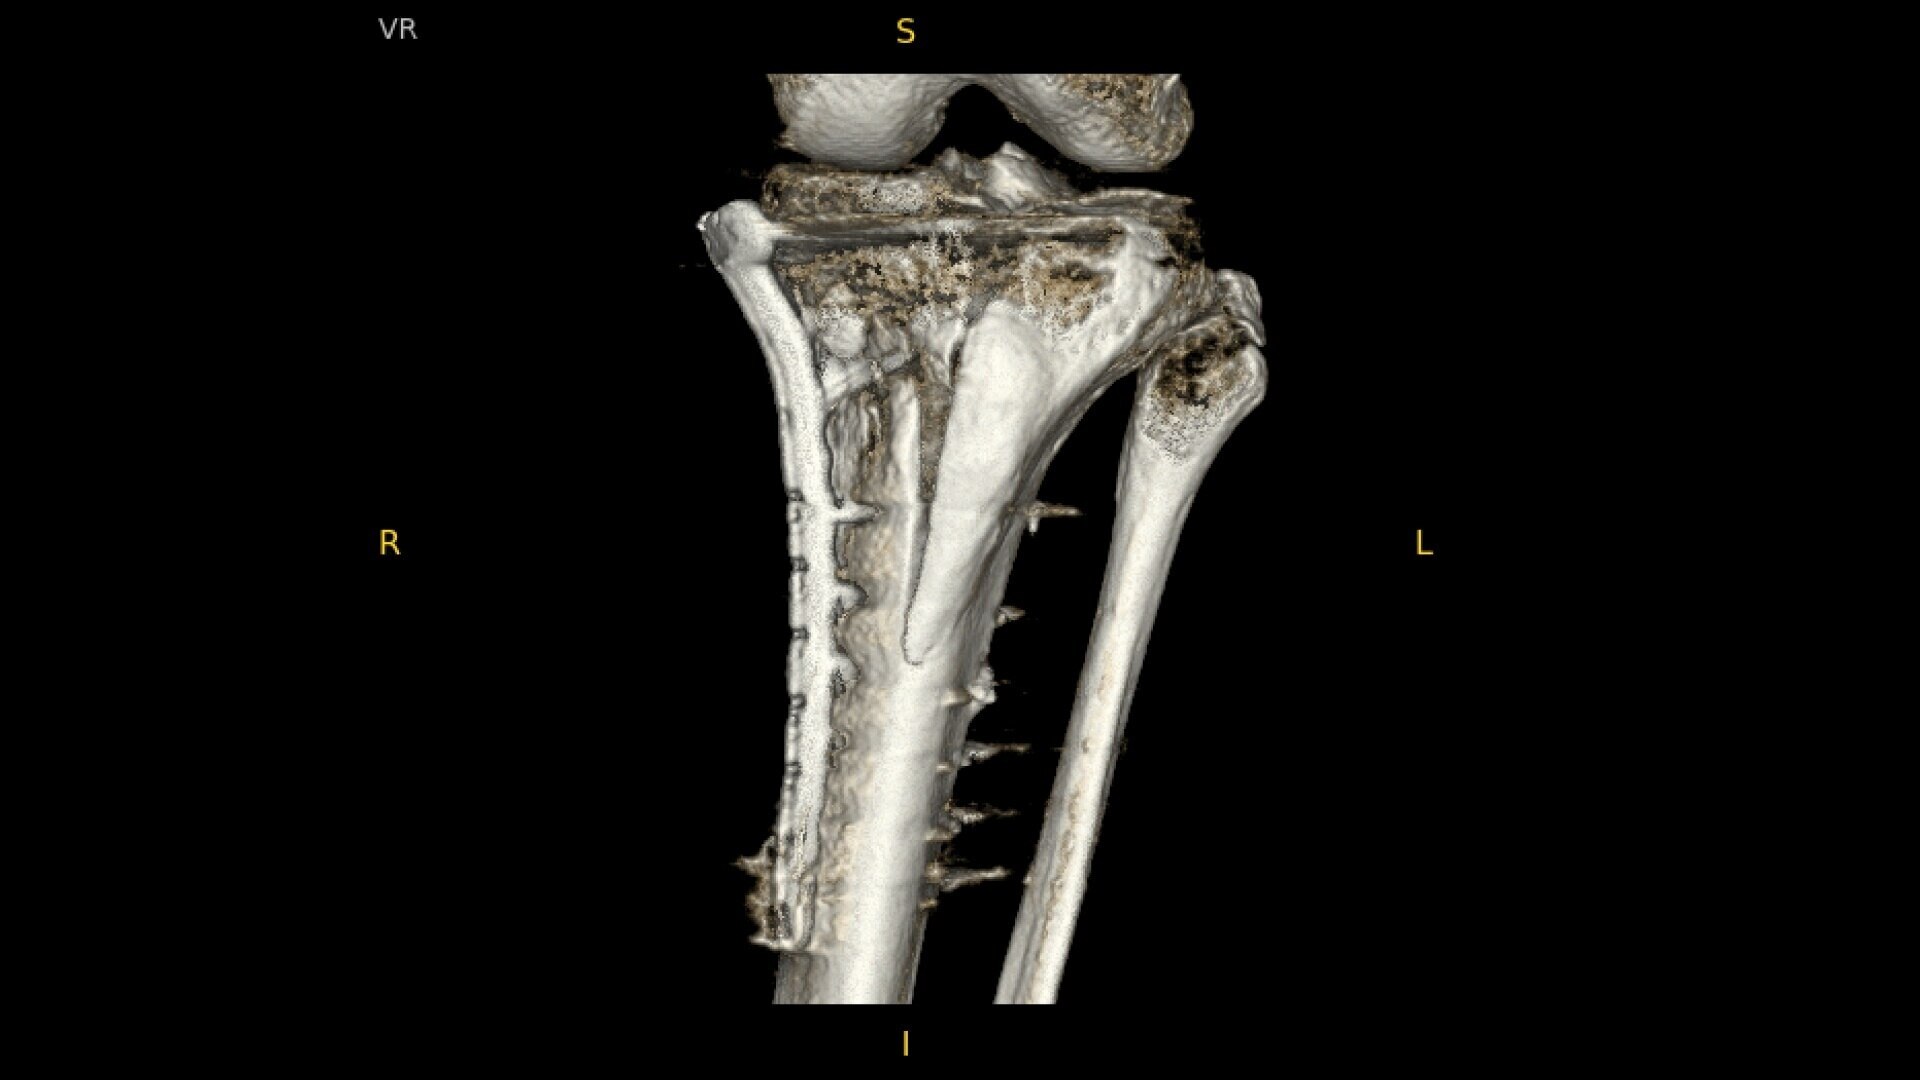

Complex orthopedic procedures require powerful imaging systems. OEC premium C-arms perform in a variety of procedures such as:

• Pilon fracture fixation

Designed to bring high-definition 3D and 2D images to surgical suites and integrating into existing surgical workflows.